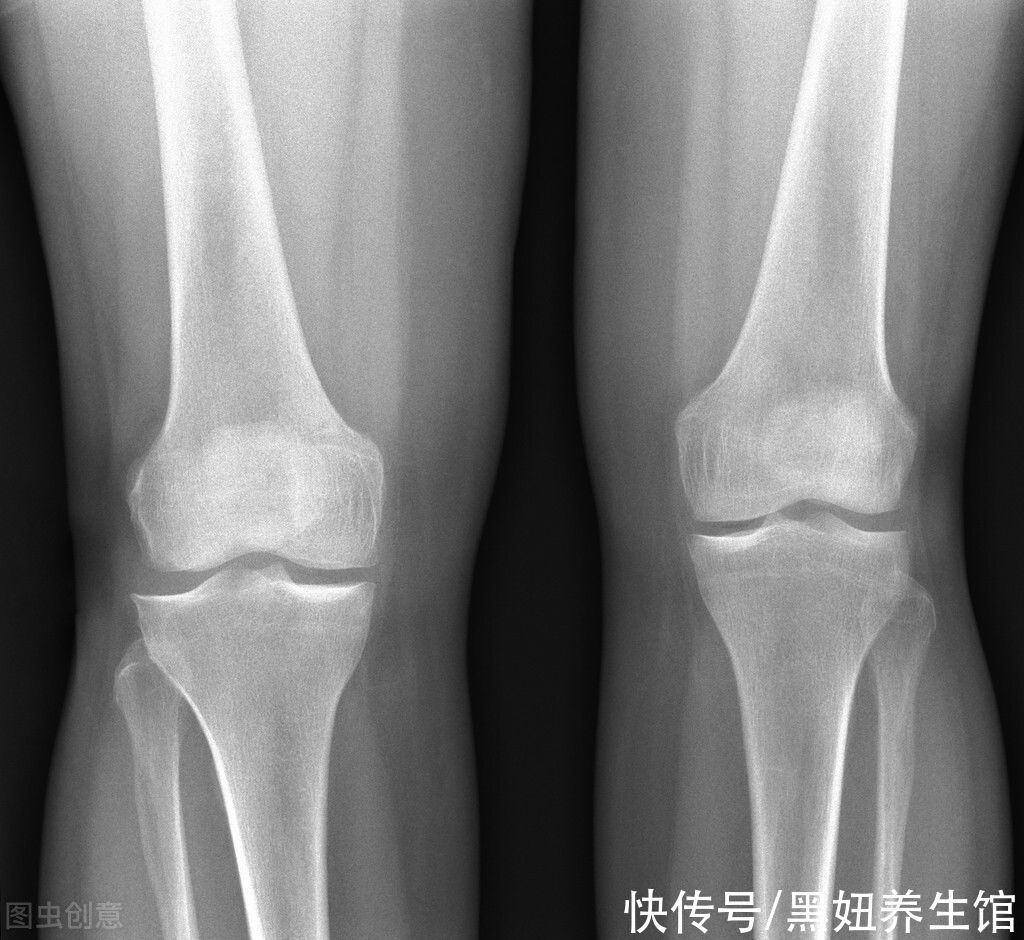

文章插图

研究发现,久坐的人患膝关节炎的几率是经常参加健身跑步的人的三倍,你是不是很震惊!这是为什么呢?

【 跑步|提醒:这个行为比跑步更伤膝盖,现在知道还不晚】正常的膝关节有一层光滑的软骨,它有很好的韧性,而且里面没有血管,所以它不能从我们身体的血液中获得任何营养,那么它靠什么来维持呢?运动!我们的软骨依靠膝关节的屈伸,然后吸收和挤出软骨中的滑液。与滑液交换营养。

因此,只有经常运动才能使膝关节软骨获得营养,维持正常的运作。如果我们长时间坐着,膝关节的软骨就会受到挤压和放松,我们也无法及时补充足够的营养,导致关节老化。